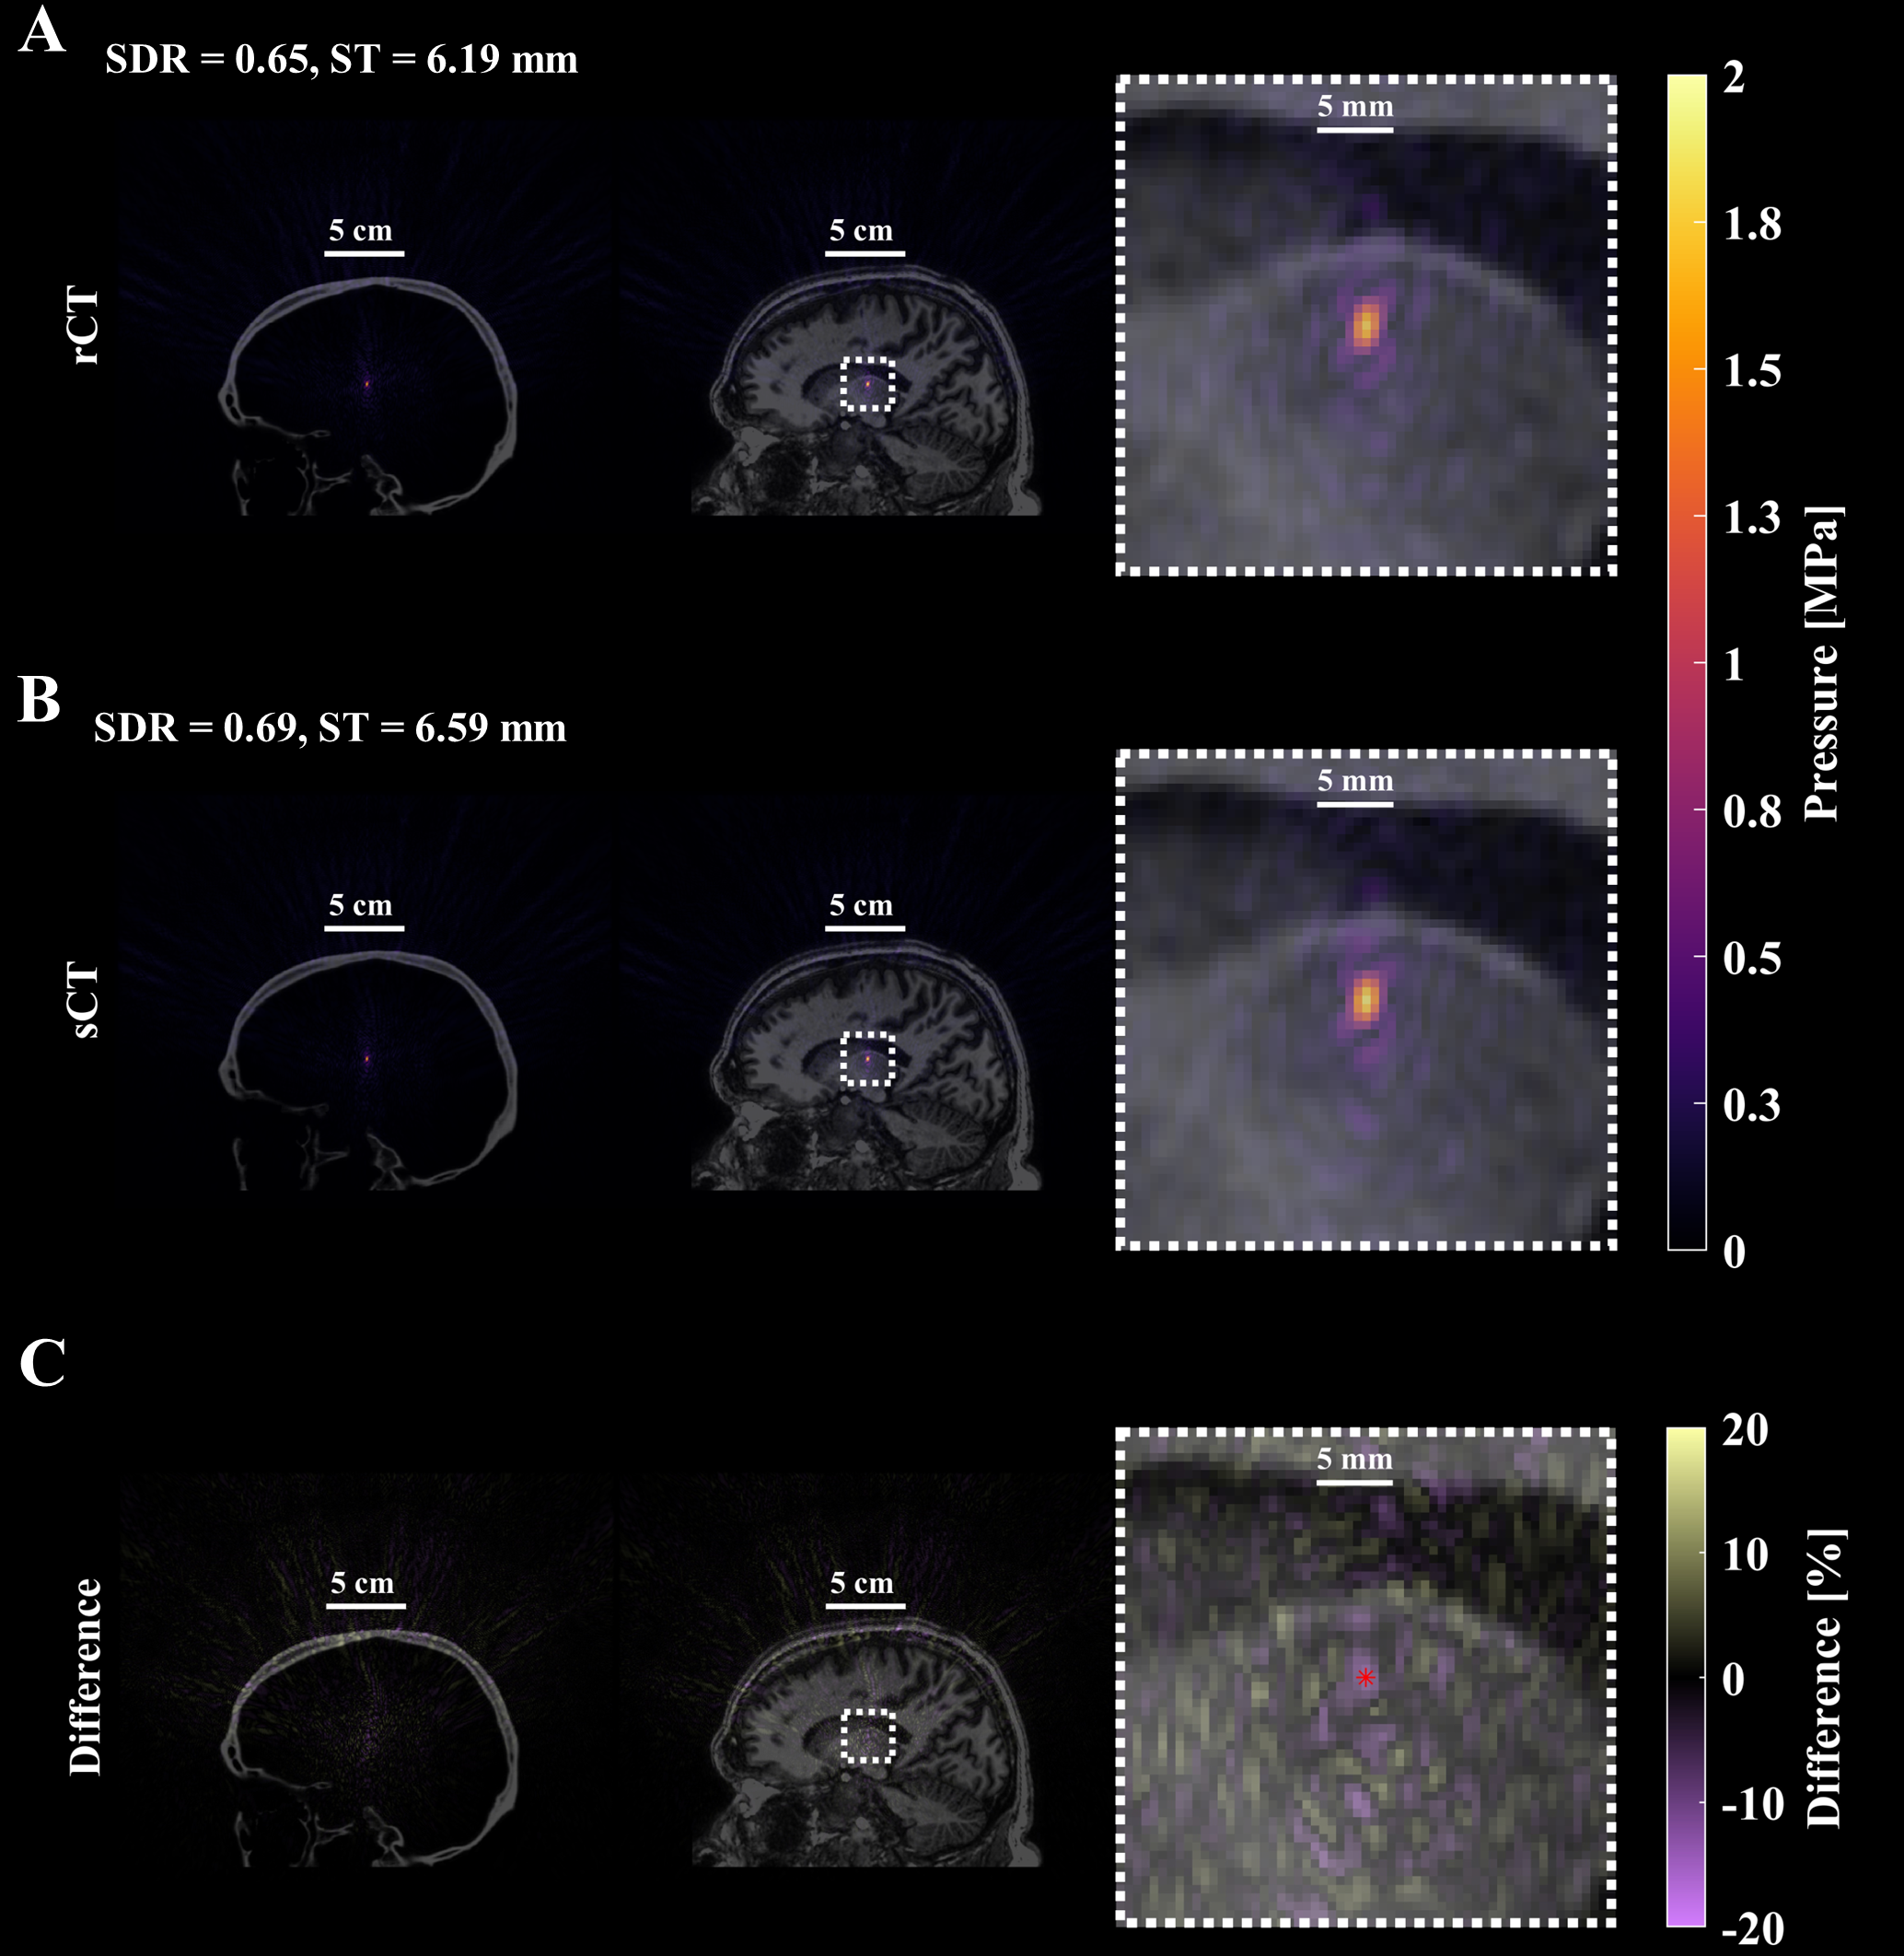

Refer to caption

Figure 8: Simulated pressure field after applying phases calculated from time-reversal. An example of the resultant pressure field from one test case with TR-corrected phases targeting the left Vim is shown (test case #13). The first row contains the pressure field simulated with the rCT skull volume, overlaid on the CT and MR images and enlarged in the final column to better see the focal shape and size (A). Similarly, the sCT skull and simulated acoustic field is presented with similar overlays (B). The percent difference of the pressure fields between rCT and sCT was calculated using the rCT peak pressure as the ground truth and presented in the final row, denoting the intended location with the red dot (C). Qualitatively and quantitatively the spatial extent of the foci are very similar between the rCT and sCT results, with the main difference identified as the maximum pressure.

Acoustic simulation results from k-Wave are summarized in Table 3. The RMS pressure at the intracranial peak and target locations were compared without phase correction and with applied phases calculated from Kranion and time reversal (Fig 7A). The mean difference in peak pressure between rCT and sCT was 12.4±8.1%plus-or-minus12.4percent8.112.4\pm 8.1\%, 7.3±6.0%plus-or-minus7.3percent6.07.3\pm 6.0\%, and 7.5±10.0%plus-or-minus7.5percent10.07.5\pm 10.0\% for no phase correction, Kranion phases, and TR corrected phases (Fig 7B). From statistical testing, we observed no difference of peak pressure between rCT and sCT simulations for the case without correction (p=0.062), but observed a difference with Kranion phases (p=0.003) and TR corrected phases (p<<0.001). Similar relationship were noted for target pressure comparisons between rCT and sCT (no correction: p=0.765, Kranion: p=0.627, TR: p=0.002). The largest distance vector between rCT and sCT peak pressure locations was noted in the case of no correction (1.3±1.2plus-or-minus1.31.21.3\pm 1.2 mm) and also the largest focal volume difference (25.5±20.5%plus-or-minus25.5percent20.525.5\pm 20.5\%) but both metrics were improved when phase correction was applied (Fig 7C-D). Kranion calculated phases reduced the distance vector of the peak location between rCT and sCT to 0.6±0.8plus-or-minus0.60.80.6\pm 0.8 and focal volume to 20.4±23.5%plus-or-minus20.4percent23.520.4\pm 23.5\%. For the TR simulations, there was no focal shift observed between rCT or sCT skulls except for one case where a 0.5 mm offset was observed (test case #10). TR simulations had the smallest difference in focal volume of 2.4±1.9%plus-or-minus2.4percent1.92.4\pm 1.9\%. An example comparing rCT and sCT’s pressure fields with TR-corrected phases is observed in Fig 8.